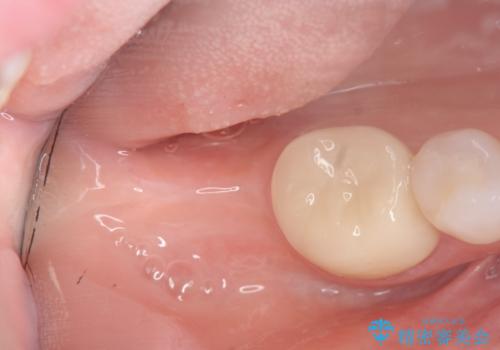

伸びてしまった上の奥歯を、神経もとらず、クラウンにもせず治療することができ、喜んでいただくことができました。